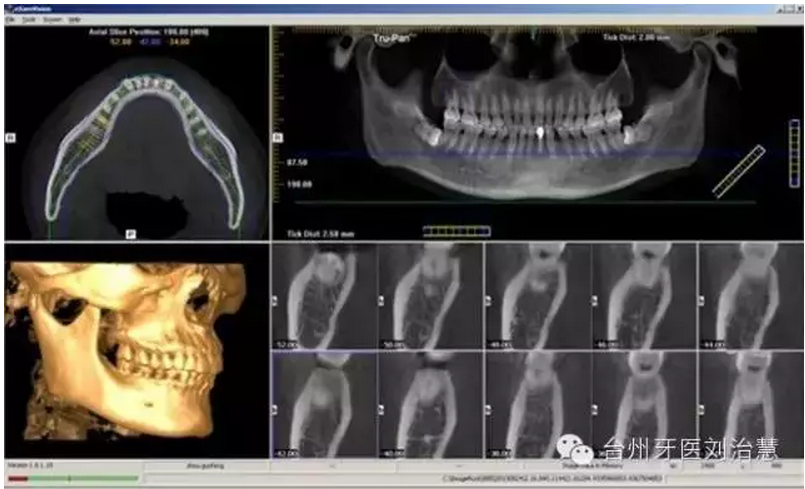

四、正畸

一次3D掃描即可獲取全部原始記錄。在正畸治療計劃制定過程中為您創(chuàng)建全景片圖像、頭顱側(cè)位片圖像等所需影像。美國的一項研究顯示,錐形束CT(CBCT)影像中可靠性和可重復(fù)性最高的解剖標(biāo)志點是頦孔、眶下孔、翼突鉤下段、樞椎齒突、寰椎橫突孔、下頜骨髁突內(nèi)部及外部、床突上部、中床突。該論文于2013年12月23日在線發(fā)表于《安格爾正畸醫(yī)師》雜志(Angle Orthod)。

總之,CBCT數(shù)秒內(nèi)完成對患者的掃描,實現(xiàn)對種植位點的快速評估,并使用嵌入工具測量可以利用的骨量,發(fā)現(xiàn)隱藏的病灶。使用自動神經(jīng)管標(biāo)記工具描繪出神經(jīng)管走行。直觀顯示骨內(nèi)阻生牙的精確位置,確定臨牙位置及毗鄰重要結(jié)構(gòu),包括神經(jīng)管、上頜竇壁和骨皮質(zhì)邊界。

CBCT卓越的清晰度和細(xì)節(jié)顯示根尖、牙冠、切端和上頜竇等各個解剖結(jié)構(gòu)。對特定解剖結(jié)構(gòu)的智能重建能夠為每位患者自動創(chuàng)建最優(yōu)的個性化圖像。

能夠以DICOM格式保存并輸出掃描數(shù)據(jù),便于臨床醫(yī)生使用各種3D設(shè)計軟件。當(dāng)使用第三方軟件制定治療計劃時,這個新工具可以大大加快工作流程,對于忙碌的牙科診療過程特別重要。